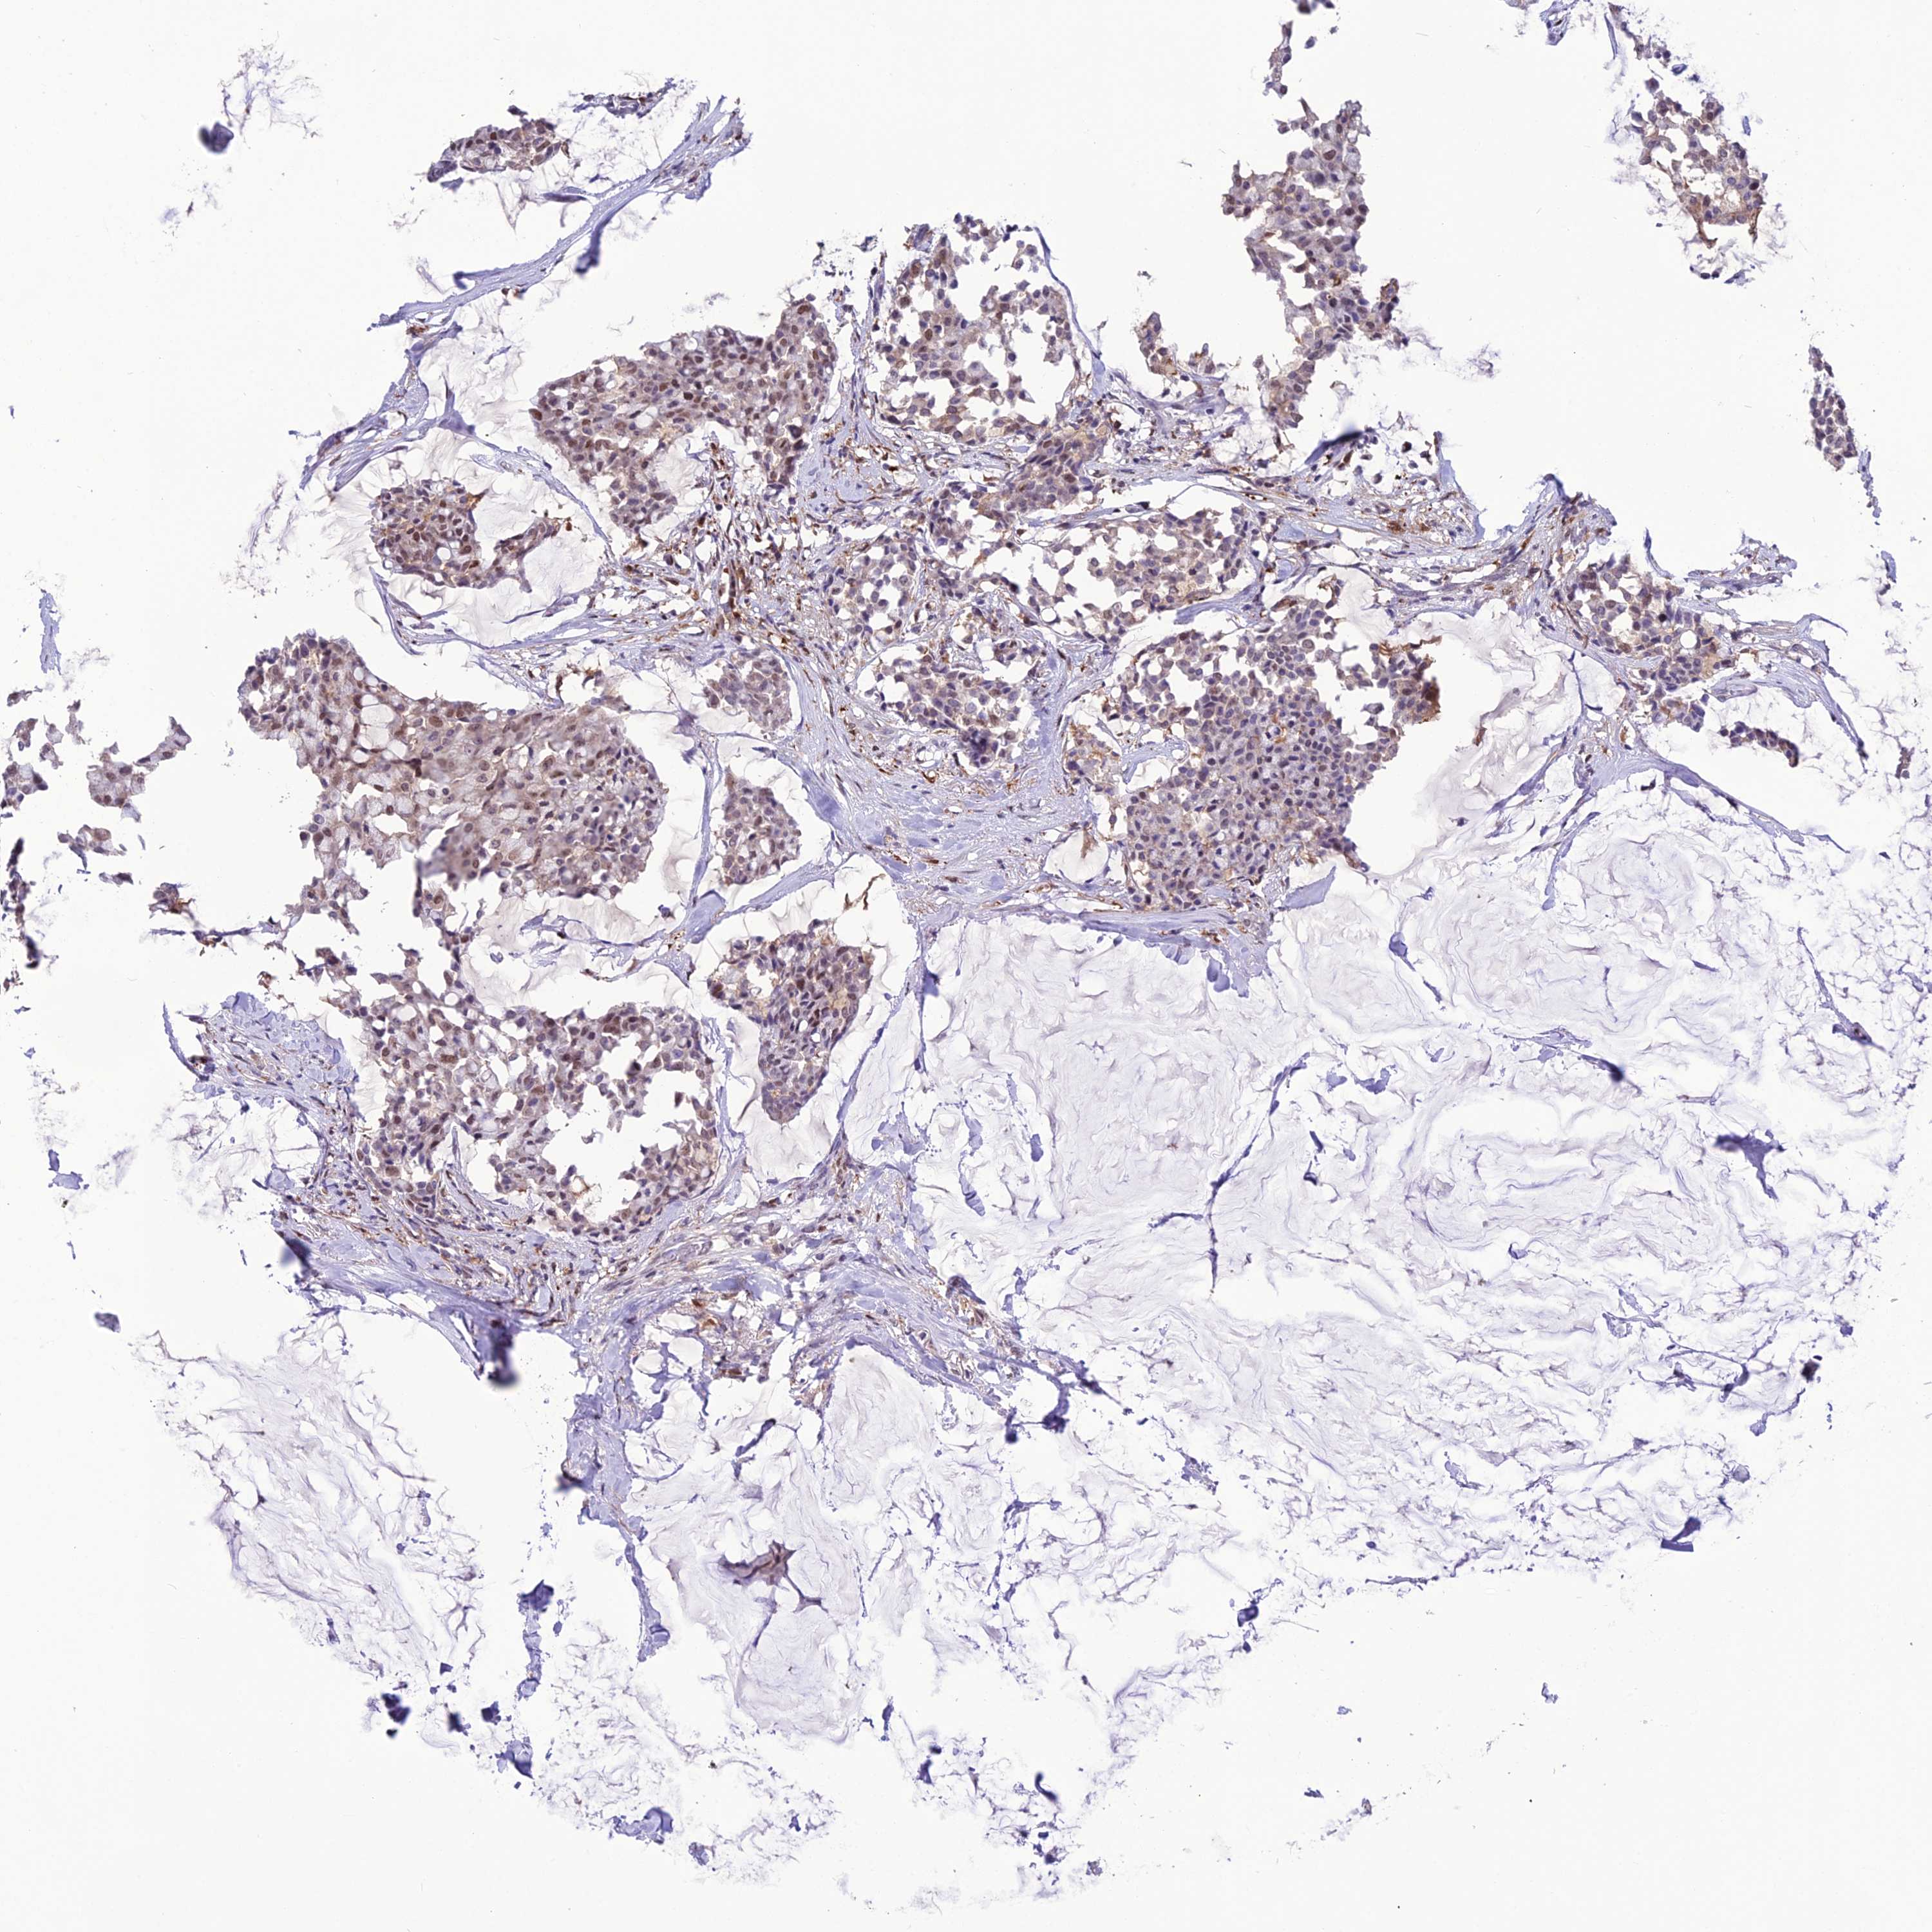

CANCER BREAST CANCER Show tissue menu

BRCA TCGA BRCA VALIDATION PROTEIN EXPRESSION